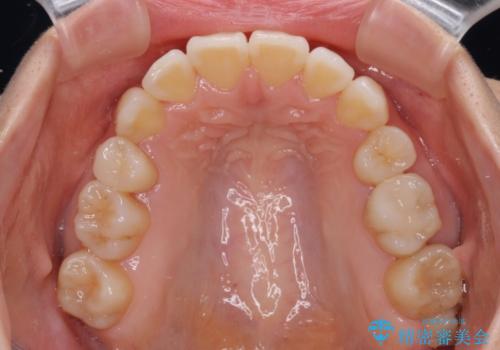

デコボコで磨きにくい歯列 ワイヤー装置での抜歯矯正で歯磨きをしやすく

- デコボコの歯列で歯磨きがしにくいことを気にして来院された患者様です。

右側の上下は歯が重なり合って、内側に移動してしまうほどであり、それに伴って正中の位置が右側にずれている状態でした。

上下左右の第一小臼歯4本を抜歯して行うことになりますが、それだけでは咬み合わせの改善や正中位置の改善が困難であると判断されたため、アンカースクリューを用いた補助装置を併用することで、スムーズかつより良い仕上がりを目指すこととしました。

途中むし歯が見つかり、矯正治療を行いながら迅速に対応し、何とか神経組織を保存して治療を終えることができました。